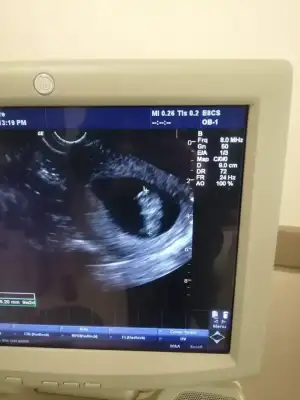

6-7 haftalık ultrason varmı yollar mısın Bi daha bakim merak ettimNisan sonu- Mayıs başıartık 18 oluyor öğreniriz heralde

ben de araya kaynasam? daha önce buraya atmıştım ama hiç tahminde bulunan olmadı.ilki 6 hafta ikincisi 7+3.6-7 haftalık ultrason varmı yollar mısın Bi daha bakim merak ettim

doktor bir şey demedi ama.Vajinal ultrason ise erkek karın ultrasonu ise kızben de araya kaynasam? daha önce buraya atmıştım ama hiç tahminde bulunan olmadı.ilki 6 hafta ikincisi 7+3.